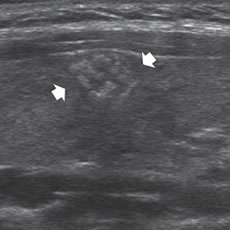

En la tiroiditis de Hashimoto el cáncer papilar puede presentarse en forma similar a un nódulo benigno, pero la ecogenicidad es algo más heterogénea, la capsula es de espesor variable y los márgenes mal delimitados (Figura 40).

Figura 40. Cáncer papilar en un paciente con tiroiditis de Hashimoto

(cabezas de flechas). La lesión es hiperecogénica con respecto

al parénquima tiroideo que es hipoecogénico, y tiene una cápsula

gruesa (cabeza de flecha). Nódulo coloideo hipocogénico, que

muestra áreas en el centro, que simula una lesión maligna.